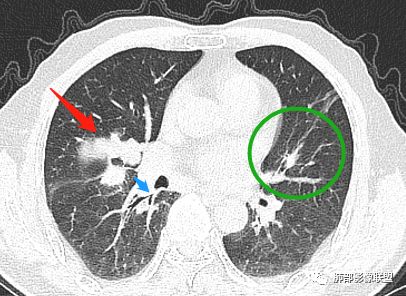

主病灶在中叶,但是左肺舌段叶有条索影,陈旧病变。蓝色箭头支气管受压,是淋巴结肿大

主病灶在中叶,但是还有结节状病变在下叶

边缘还有多发小灶

病灶明显平直,中央是粘液栓,低密度,分界清楚

吴婧老师和南边老师都对该病例进行了深入分析。从支气管管壁的增厚,支气管狭窄后扩张,支气管粘液栓,病灶形态,到病灶不均匀强化及坏死彻底,到周边病灶及肺组织空气的潴留,加之纵隔内淋巴结肿大伴钙化等等,都支持慢性炎性病灶,尤其是结核。

现在小编来增加一个炎性另一个征象,是我们王兆宇老师原创的----就是墨西哥仙人掌征。

墨西哥仙人掌征---结核        影像上结核灶,粗大的均匀枝干,推测是支气管囊状扩张引起的,在非支气管区,形成圆形坏死囊群;如果这些坏死比较稀薄,又遇到扩张支气管,就会形成粗大的“墨西哥仙人掌”。结核引起的支气管近端炎症纤维化,可以造成支气管阻塞,从而将干酪样坏死物封堵在管腔内。仙人掌主干内部应该是干酪为主,稀薄的,具有流动性,时间久了会出现钙化。

结核坏死与鳞癌鉴别有一点是结核坏死没有方向性,鳞癌有。鳞癌靠近支气管近端部分,血供容易维持,不易坏死,所以坏死靠外侧。而结核干酪样坏死,把一定体积的流动性坏死物,包裹起来,什么形状最省料?坏死物包裹,表面积最省的自然是圆球形,而遇到支气管,坏死物一多,就把支气管撑大了。包裹物是就地取材,扩张的支气管就成了包裹结构。